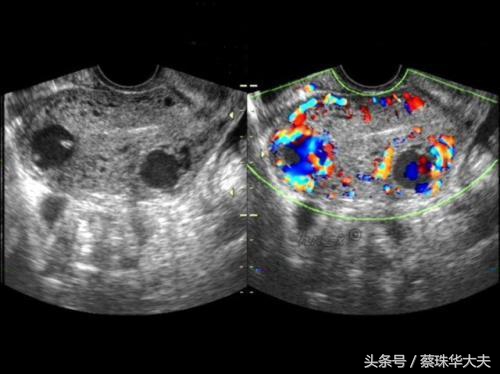

黄体囊肿特点里面回声有点杂,B超会经常描述成混合性回声。如果当月排出来的卵没有怀孕,那黄体囊肿就没有任务了,就自行萎缩掉。

包括 卵巢肿瘤,卵巢巧克力囊肿,附件炎症性包块。

这些囊肿的特点是月经干净后复查,囊肿不会缩小,大小不变或会增大。或者B超下看上去回声乱糟糟。这些囊肿需要及时的治疗。